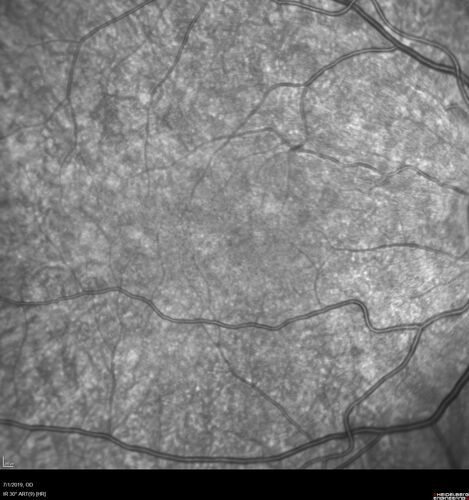

Ocular Lymphoma - Initially presented like auto-immune retinopathy

43 year old man: initial presentation - The vision in the left eye is blurry and opaque for about 2 weeks.  In the central of the vision, when he covers the right eye, in the center of the left eye there is a film with a light in the middle.  This has never happened before.  He has not been sick for the last few months.  A few weeks ago he saw waves on the floor when looking down but that has gone away.  Since the vision loss started the vision has not changed much.  The central vision is not getting better.

VA improved over 2 months to normal.  Then the patient had 2 more episodes of self-limited vision loss (no treatment).  Then 2 years later he presented with a diagnosis of CNS lymphoma and later developed subretinal deposits (last images)